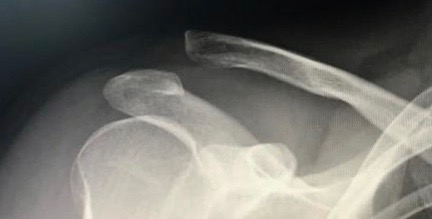

Des radiographies centrées sur l’acromioclaviculaire permettent de constater cette disjonction.

Les disjonctions acromio-claviculaires sont fréquentes, lors d’un choc direct sur le moignon de l’épaule notamment lors de sports comme le rugby, les sports de combat, le ski ou le vélo. Le patient se plaint d’une douleur et d’une impotence fonctionnelle. L’épaule présente une déformation douloureuse de l’articulation acromio-claviculaire avec parfois la clavicule sous la peau. Dans les

cas les plus graves, il est objectivé une mobilité verticale en touche de piano et un tiroir antéropostérieur. A long terme, une arthrose acromio-claviculaire peut apparaître.

L’articulation acromio-claviculaire est entourée d’une capsule renforcée de ligaments acromioclaviculaires qui assurent la stabilité horizontale. La stabilité verticale est assurée par des ligaments coraco-claviculaires (ligaments conoïde et trapézoïde). La disjonction peut être définie grossièrement en plusieurs stades :